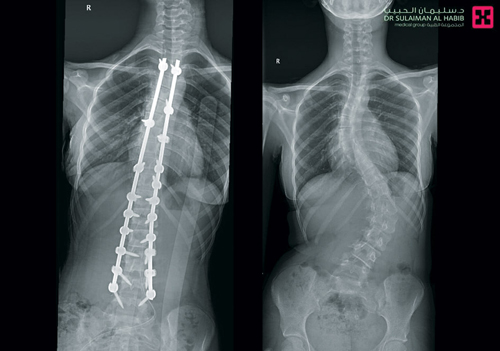

وأكد الدكتور عوض أن نتائج الفحوصات أشارت إلى وجود اعوجاج شديد في منطقة الفقرات القطنية شديد يبلغ زاويته 76 °، إضافة إلى تقوس آخر في الفقرات الصدرية بلغ انحنائه 58° مع تشوه وبروز في منطقة الصدر والبطن. مشيراً إلى أن الفريق الطبي المعالج قام بدراسة وافية للحالة وقرر التدخل الجراحي للحد من المضاعفات والمتمثلة في ازدياد شدة التقوسات بالعمود الفقري والأعراض المصاحبة له في حالة التأخر بالعلاج.

وأضاف الدكتور عوض أنه تم استخدام أجهزة وتقنيات متطورة للمساعدة في تعديل وتقويم الفقرات في عملية استغرقت 3 ساعات، وتم فيها تعديل الجنف بنسبة 100 % للفقرات القطنية وبنسبة 96% لفقرات الصدر، علاوة على تعديل وتقويم عظام الحوض بصورة جيدة.